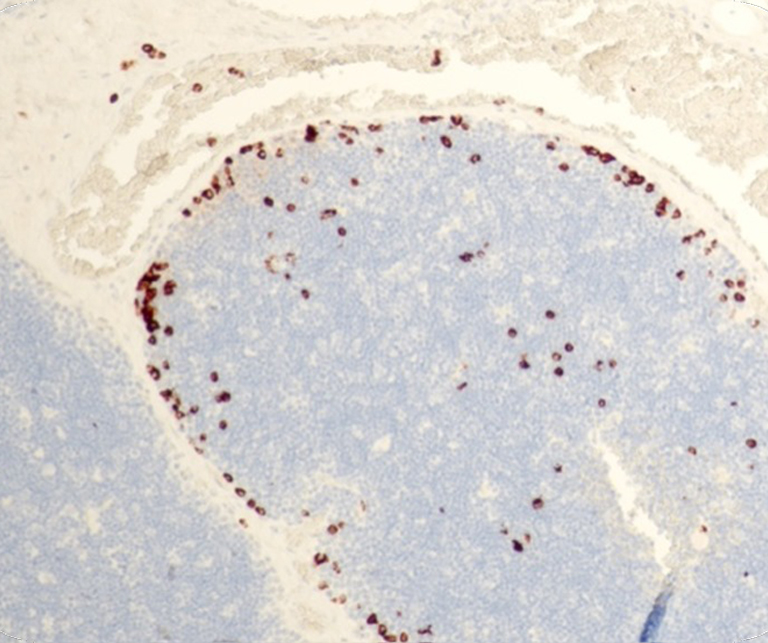

Vascular Pathology

General Marker

Hematopathology